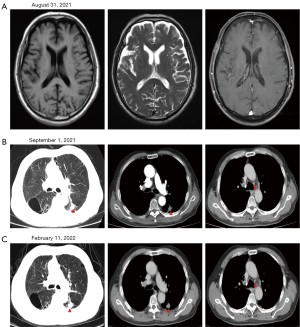

On Aug 31, 2021, the cranial enhancement MRI was repeated, and the comparison with the previous film revealed no brain metastasis (Figure 2A). Chest enhanced CT was repeated on Sep 01, 2021, and a mass was seen in the dorsal segment of the left lower lobe of the lung, approximately 29 mm ×24 mm in size (Figure 2B). Targeted therapy with crizotinib 250 mg bid was continued.

On Feb 11, 2022, a repeat chest enhanced CT scan showed a mass approximately 28 mm ×24 mm in size in the dorsal segment of the left lower lobe of the lung, and the evaluation of partial remission (PR) (Figure 2C) was unchanged in comparison with the previous scan. The patient did not experience any adverse events, such as abnormal liver function, during oral crizotinib therapy. All procedures performed in this study were in accordance with the ethical standards of the institutional and/or national research committee(s) and with the Helsinki Declaration (as revised in 2013). Written informed consent was obtained from the patient for the publication of this case report and accompanying images. A copy of the written consent is available for review by the editorial office of this journal.